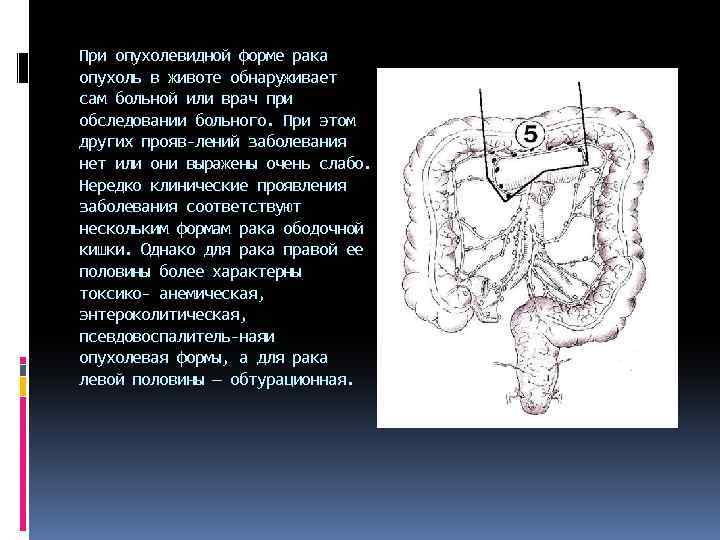

При опухолевидной форме рака опухоль в животе обнаруживает сам больной или врач при обследовании больного. При этом других прояв лений заболевания нет или они выражены очень слабо. Нередко клинические проявления заболевания соответствуют нескольким формам рака ободочной кишки. Однако для рака правой ее половины более характерны токсико анемическая, энтероколитическая, псевдовоспалитель наяи опухолевая формы, а для рака левой половины — обтурационная.